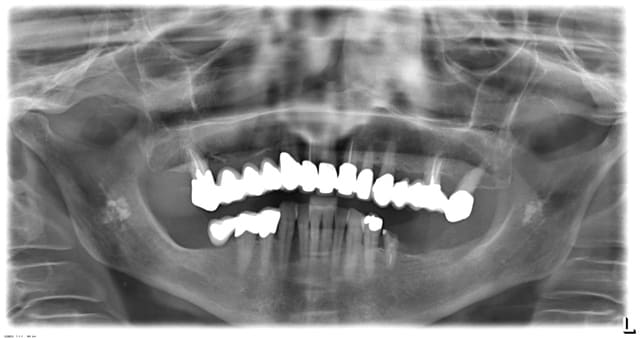

J'ai vu ceci sur un OPG (ci-joint)dernièrement, des calcifications à gauche et à droite au niveau de l'angle mandibulaire autour du n. mandibulaire.

Asymptomatique et pas de signes cliniques, patiente de 70 ans....

il sagit probablement d atheromes carotidiens bilateraux

Euh justement vu le siège des calcifications sur ton document (4ème vertèbre sous la corne hyoïdienne), et la répartition des taches sur la pano, je pencherai aussi pour une lithiase parotidienne bilatérale.

Il s'agit certainement de tonsilithes bilatéraux, trop en avant pour la parotide d'après moi.